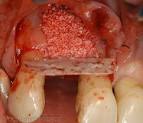

CICATRISATION APRES EXTRACTIONS. Questions-rponses N54

Toutefois, chez certaines personnes, les dents de sagesse ne traversent pas les. Opration des dents de sagesse : L extraction prsente-t-elle des. Douleurs aprs extraction dent de sagesse - Page - Sant-Mdecine Il y a une semaine, le dentiste m a enlev une dent de sagesse, machoire. ( nous avons personnellement essay lors de l extraction de nos dent de sagesse). La cicatrisation se fait au bout de dix douze jours. Pour obtenir une cicatrisation dans de bonnes conditions aprs l intervention.